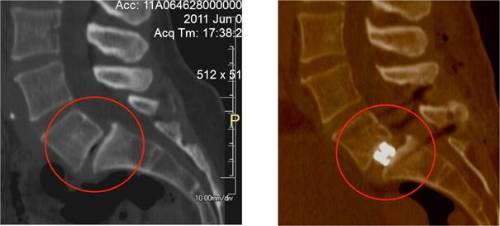

Postoperative CT scan images showing an extremly collapsed L5/S1 disc (left) and the

same disk’s restored height after insertion and expansion of an expandable cage (right)